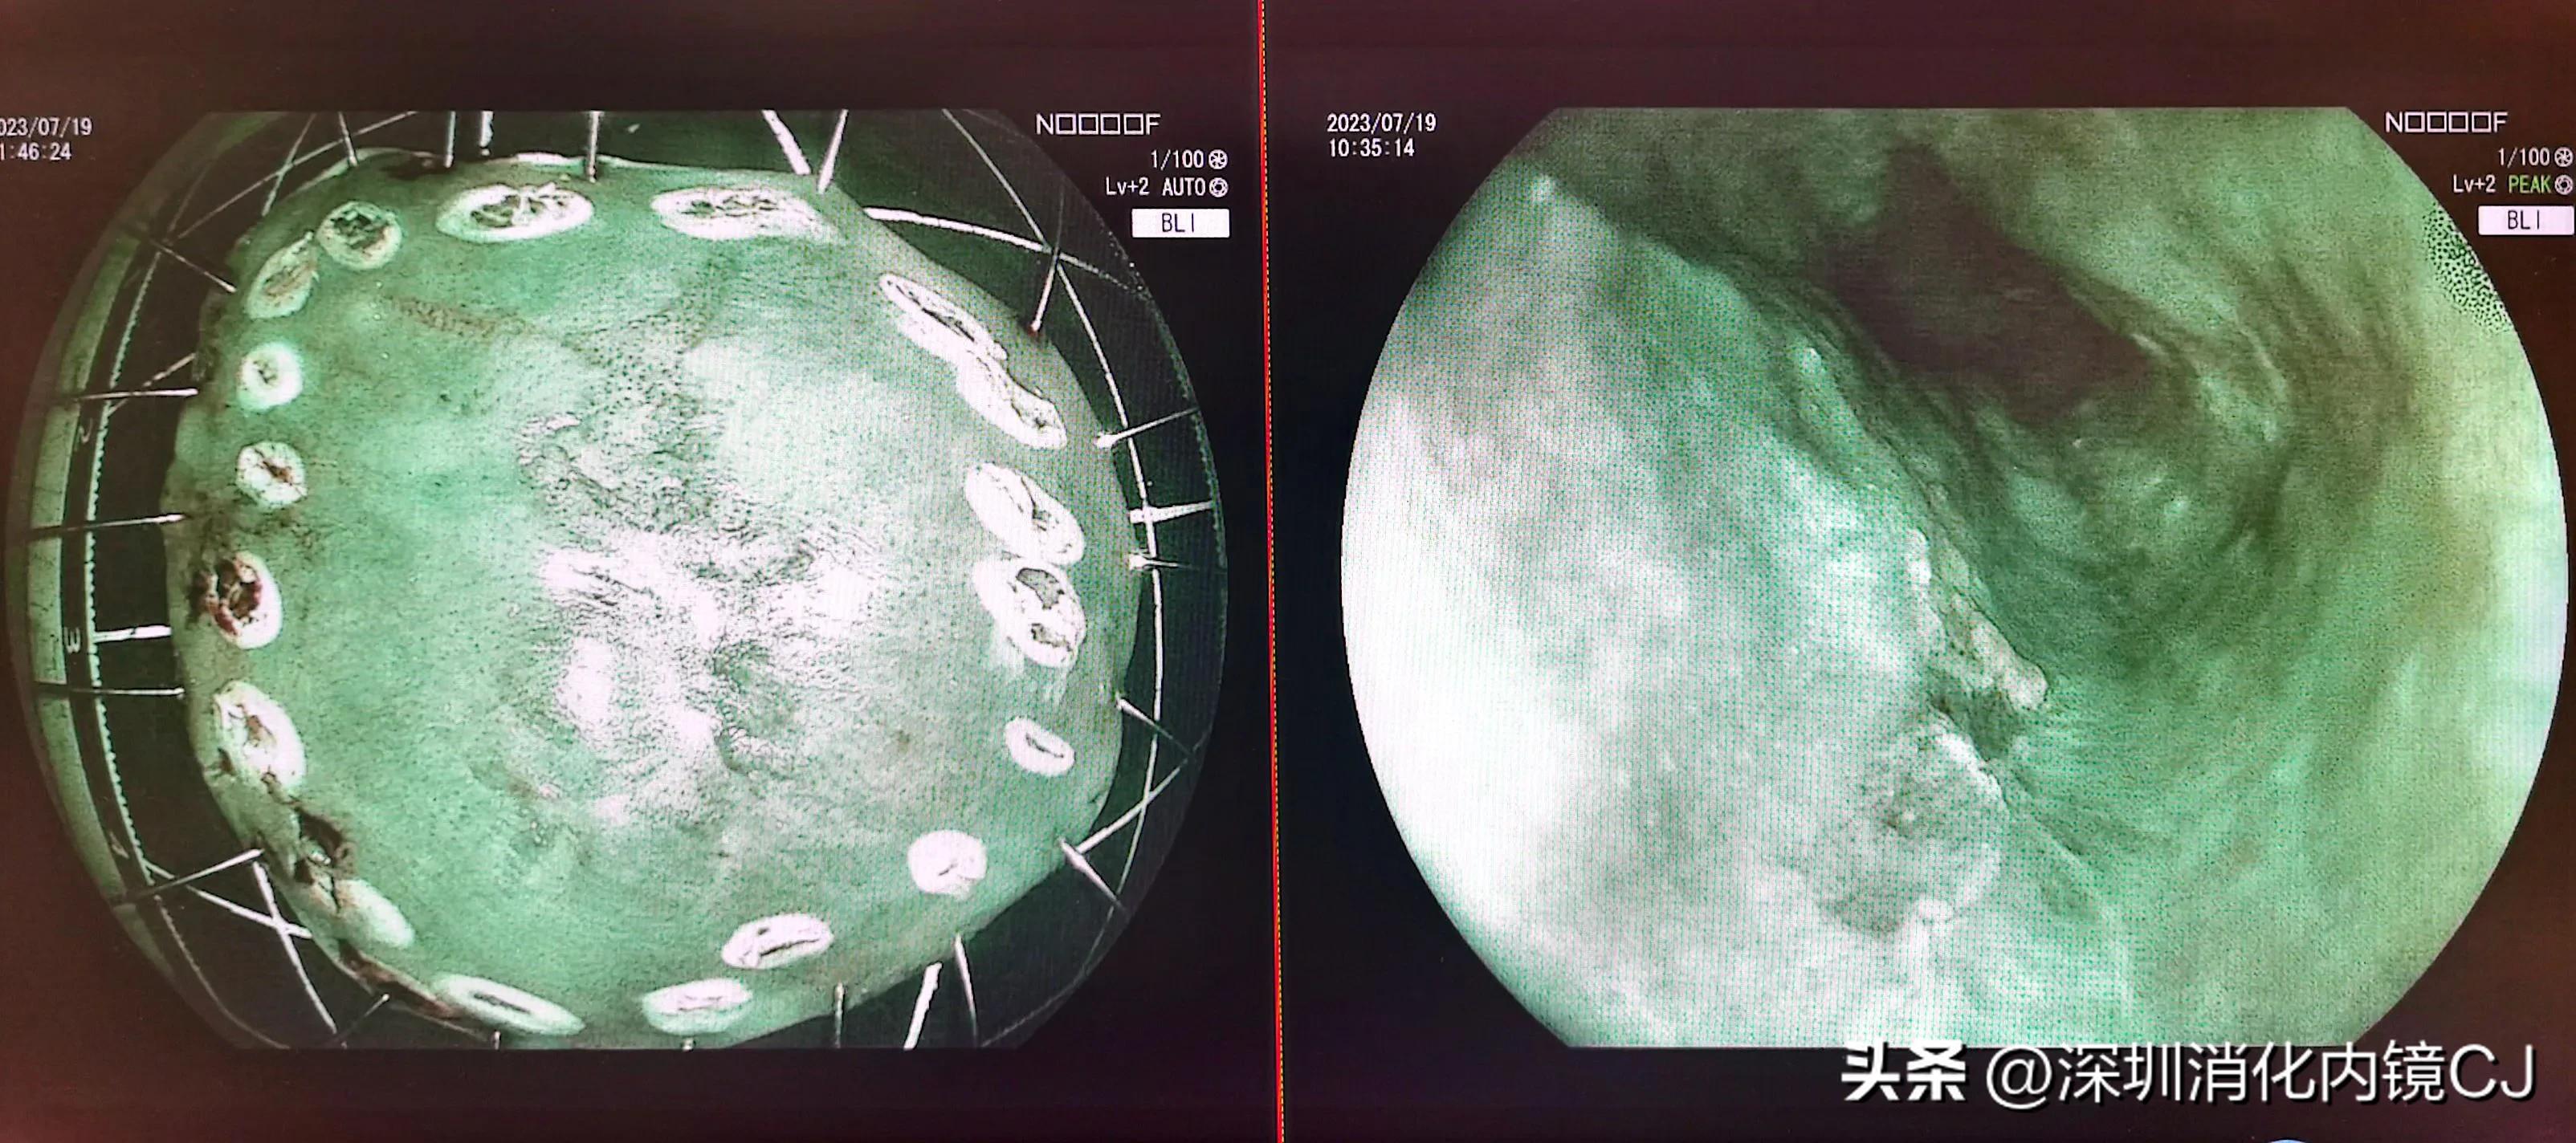

粘膜切开刀标记,并剥离病变及周围粘膜

食管癌黏膜被剥离

病理证实为早期食管癌